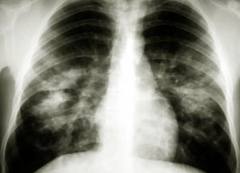

This is a possible complication of which STD? How would the patient present?

Chlamydial cervicitis/urethritis (or LGV?)

Repetitive staccato cough, peripheral eosinophilia, no fever or wheezing

(Infantile pneumonia; notice bilateral infiltrates + hyperinflation)